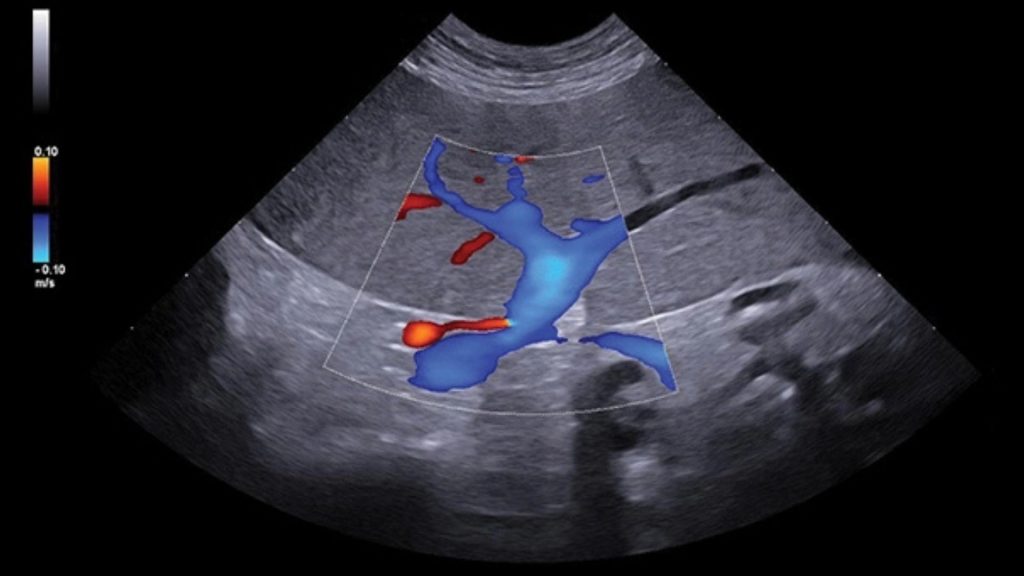

Safra kesesi;

Ultrasonografi, veteriner hekimlikte safra kesesi hastalığının teşhisinde en sık kullanılan tanısal görüntüleme aracıdır. Safra kesesi ve safra sisteminin muayenesi, karaciğer ve çevresindeki karın anatomisinin rutin ultrasonografik incelemesinin bir parçası olarak dahil edilmelidir. Safra kesesi muayenesi ve hasta hazırlığı endikasyonları karaciğer için açıklananlarla aynıdır. Safra kesesi safra için bir rezervuar görevi görür ve çoğu hastada orta hattın hemen sağında yer alan, yuvarlak/oval ila gözyaşı damlası şekilli bir yapı olarak görünür. Bazı kedilerde safra kesesi iki loblu olabilir. Safra kesesinin boyutu değişkendir ve hayvanın ne zaman beslendiğine bağlı olarak değişebilir. Yemekten sonra safra kesesinin kasılmasına neden olan enzimler salgılanır. Anoreksik veya aç hastalarda safra kesesinin hacmi artar. Safra kesesi lumeni, değişen miktarda safra çamuru (sediment) içerebilir. Safra çamurunun varlığı, safra kesesinin boşalmasının geciktiğini gösterebilir ve kedilerde karaciğer enzimlerindeki artışın göstergesi olabilir. Safra kesesi duvar kalınlığındaki artışın pek çok sebebi olabilir. Bunlar kolesistit/kolanjiohepatit, hepatit veya pankreatit gibi çevredeki anatominin iltihaplanması, hipoproteinemi, sağ taraflı konjestif kalp yetmezliği, portal hipertansiyon veya safra yolu tıkanıklığının neden olduğu duvar ödemi, kistik hiperplazi, safra kesesi polipleri, ve neoplazilerdir.

Karaciğer ultrasonografisinde, hepatik parankim (karaciğer dokusu), büyük hepatik ve portal damarlar, bitişiğinde caudal vena cava ve safra kesesi ve bilier sistem incelenir. Radyografiden farklı olarak ultrasonografi, hedef yapıların çeşitli düzlemlerden görüntülenmesine olanak sağlar. Karaciğerin ultrasonografik muayenesi sırasında hekimin tercihine göre hasta sağ yan, sol yan veya sırt üstü pozisyonlarında yatabilir. Daha iyi görüntü alınabilmesi için karın bölgesi göğüs bölgesine kadar tıraşlanıp temizlenmelidir. Görüntü kalitesini hastanın vücut yapısı, karaciğerin boyutu ve gastrointestinal içerik etkileyebilir. Mide içeriğindeki gaz iyi bir karaciğer görüntülemesinin önündeki en önemli engeldir. Bu sebeple hastanın aç olarak muayene getirilmesi tercih edilir. Karaciğer ultrasonografisine ihtiyaç duyulan durumlar, karaciğer hastalıklarıyla ilişkili klinik belirtiler (kusma, ishal, abdomende genişleme, abdomenin elle muayenesinde karaciğer boyutunun arttığının farkedilmesi vs.), laboratuvar analizlerinde biyokimyasal değişiklikler (ALT, ALP, AST, NH3, GGT, BİLİRUBİN, TOTAL PROTEİN, ALBUMIN), ikterus (sarılık), hepatomegali, asites, akut abdomen veya abdominal kitle şüphesi, metastatik kitle şüphesi, hepatik enseflaopati, immun sistem hastalıklarını içermektedir. Hepatik arterleri ve intrahepatik dallarını görüntülemek için Doppler muayenesi gereklidir. Doppler ultrasonografi ile hepatik arter, portal ven ve caudal vena cava incelenebilir. Konjenital veya edinsel Portasistemik Şantla (PSŞ) ilişkili klinik veya laboratuvar belirtileri olan hayvanlarda intrahepatik veya ekstrahepatik anormal damarlar da saptanabilir. Doppler görüntüleme ile aynı zamanda intrahepatik portal hipertansiyonun da tanısı konulabilmektedir.